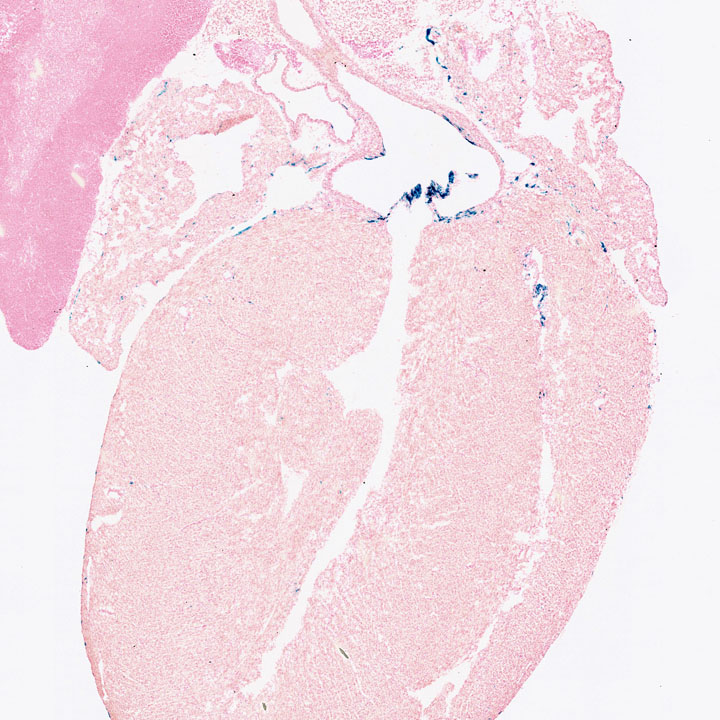

Images

Drag images to compare to others or to data in the table below. Drag corners to resize images for more detail.

Recombinase Activity